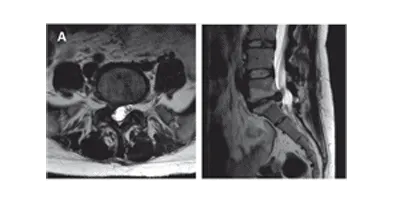

Les douleurs radiculaires sont provoquées par l’irritation et l’inflammation d’une racine nerveuse ou de son ganglion spinal. La douleur prend son origine dans la région lombaire pour irradier typiquement dans la fesse et le membre inférieur selon une distribution dermatomale. Il s’agit d’une douleur persistante aiguë, tranchante, aggravée par les mouvements, la toux ou les éternuements. L’étiologie la plus fréquente est la hernie discale (figure 8.2). Le mécanisme pathophysiologique est plus inflammatoire que compressif. L’irritation de la racine nerveuse dans le foramen intervertébral par des modifications dégénératives (sténose foraminale) est également possible.

Figure 8.2. Hernie discale S1 droite (A) et L3 gauche (B), à l’origine de douleurs radiculaires.

La douleur radiculaire n’est pas synonyme de radiculopathie. La radiculopathie est définie comme une altération de la conduction d’une racine nerveuse, pouvant se manifester par des déficits sensitifs ou moteurs, ou par des paresthésies. Les déficits moteurs (parésie ou paralysie) suivent une distribution myotomale alors que les déficits sensitifs (hypoesthésie ou anesthésie) ont une distribution dermatomale. Une radiculopathie n’est pas forcément accompagnée d’une douleur radiculaire et inversement.

Contrairement à la croyance populaire, il est souvent difficile de différencier cliniquement les hernies discales L4, L5 et S1 lorsqu’il n’existe qu’une douleur radiculaire. C’est souvent la radiculopathie qui permet de préciser l’atteinte, grâce à la distribution des troubles sensitifs et aux modifications des réflexes ostéotendineux (L3 et L4 pour le réflexe rotulien, et S1 pour le réflexe achilléen).